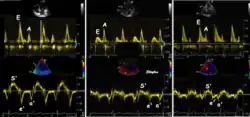

Diastolic function

As the ventricle relaxes, the annulus moves towards the base of the heart, signifying the volume expansion of the ventricle. The peak mitral annular velocity during early filling, e' is a measure of left ventricular diastolic function, and has been shown to be relatively independent of left ventricular filling pressure.[12][13][14] If there is impaired relaxation (Diastolic dysfunction), the e' velocity decreases. After the early relaxation, the ventricular myocardium is passive, the late velocity peak a' is a function of atrial contraction. The ratio between e' and a' is also a measure of diastolic function, in addition to the absolute values.

During the two filling phases, there is early (E) and late (A) blood flow from the atrium to the ventricle, corresponding to the annular velocity phases. The flow, is driven by the pressure difference between atrium and ventricle, this pressure difference is both a function of the pressure drop during early relaxation and the initial atrial pressure. In light diastolic dysfunction, the peak early mitral flow velocity E is reduced in proportion to the e', but if relaxation is so reduced that it causes increase in atrial pressure, E will increase again, while e', being less load dependent, remains low. Thus, the ratio E/e' is related to the atrial pressure, and can show increased filling pressure[15][16] although with several reservations.[17][18] In the right ventricle this is not an important principle, as the right atrial pressure is the same as central venous pressure which can easily be assessed from venous congestion.[19][20]